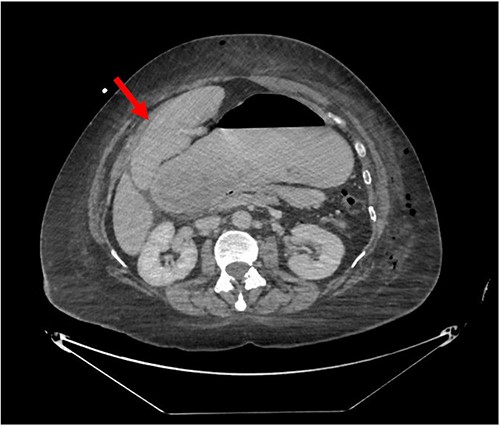

Despite the insertion of the NGT yielding 1500 cc output in 24 hours, the patient continued to experience severe abdominal pain. Urgent abdominal and pelvic computed tomography (CT) scans were taken, as seen in Figs 2–4. The CT scans showed gastric distension and the spleen positioned anteriorly in the right upper quadrant. Consequently, the decision was made to promptly bring the patient to the operating room for a diagnostic laparoscopy with plan to detorse the spleen.

CT of the abdomen and pelvis (sagittal slice) showing gastric distention and the spleen positioned anteriorly.

CT of the abdomen and pelvis (axial slice) showing gastric distention and the spleen positioned anteriorly in the right upper quadrant.